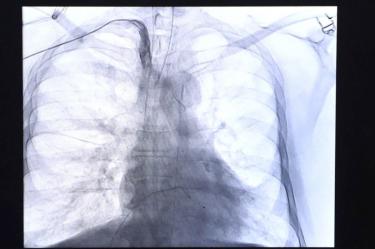

Enfermedades del corazón se mantienen como la primera causa de muerte en los mexicanos

Con 100 mil 710 decesos durante el primer semestre del 2024, las enfermedades del corazón se mantuvieron como la principal causa de muerte de los mexicanos.

Los hombres presentaron la mayor mortalidad con 53 mil 515 fallecimientos, frente a los 47 mil 187 que se registraron entre las mujeres.